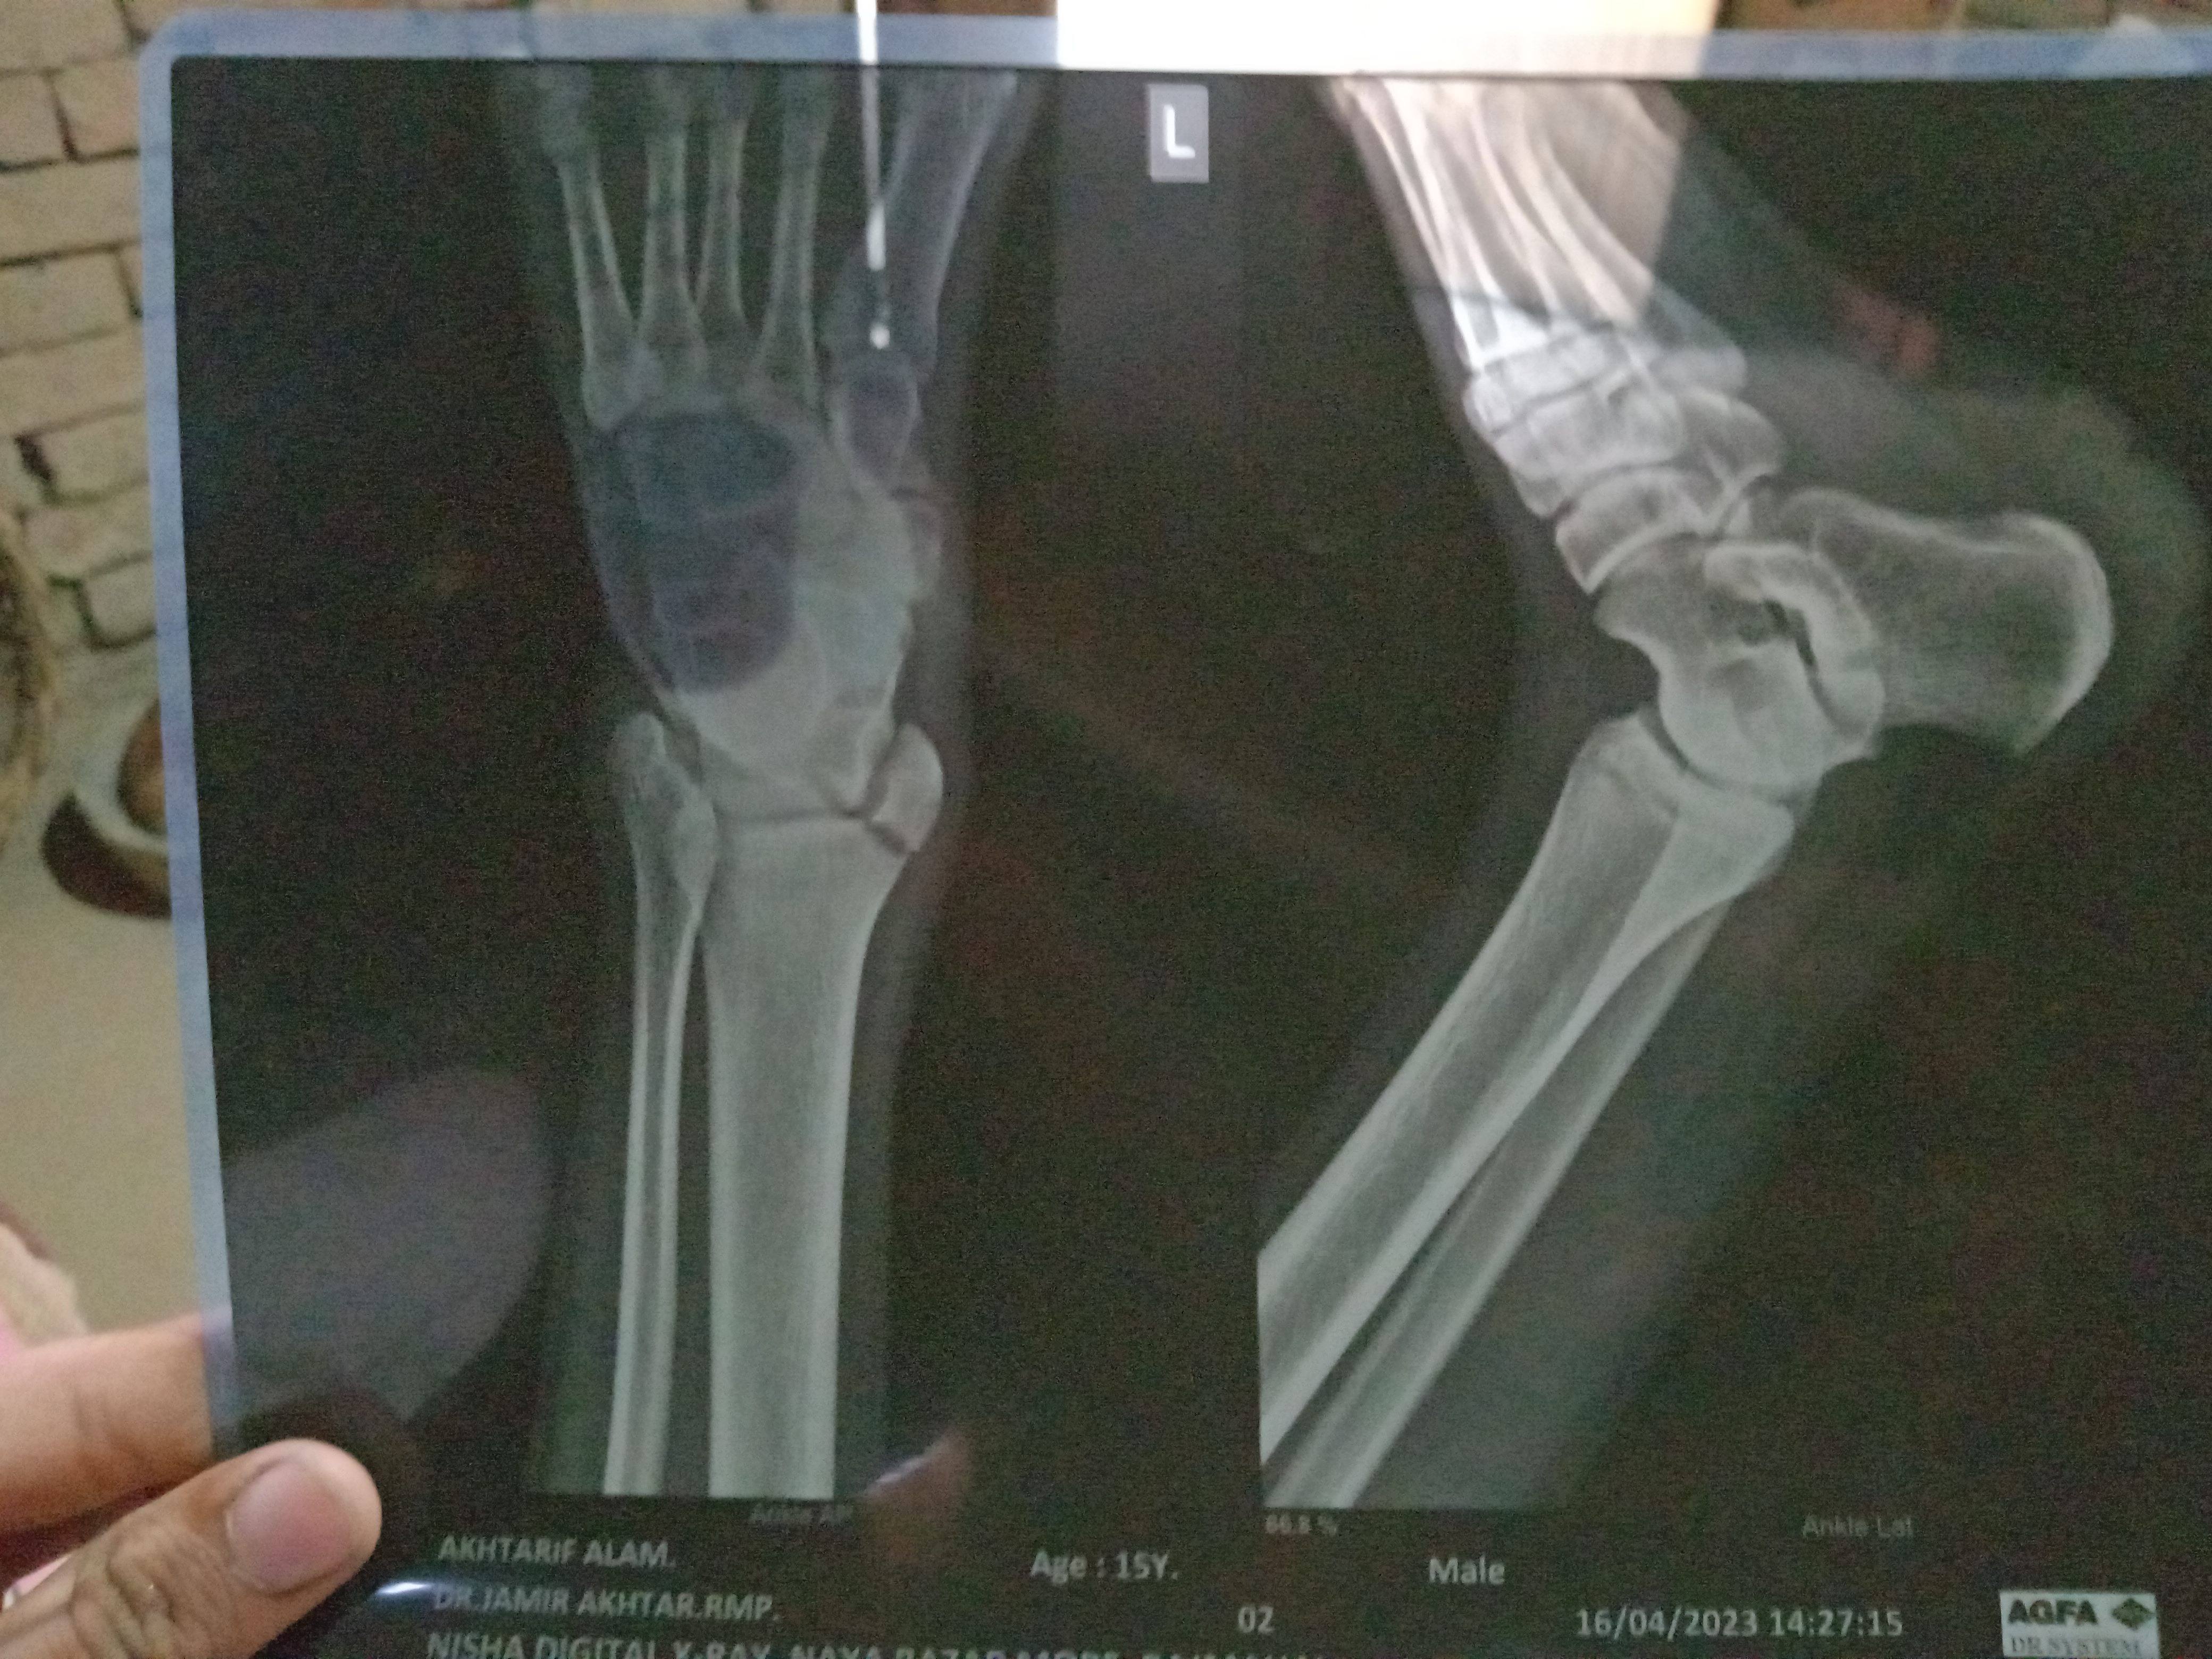

Sir लगभग मैं 15-20 हो गया ऊपर से गिर गए थे जिससे कुछ दिन तो चलने में दिक्कत आई पर अभी उतना दिक्कत नहीं होती लेकिन सूजन काफी हैं इसे मालिश करके लिए था Sir आज X- RAY किया हूं तो अन्दर वाली हड्डी टूटी हुई हैं